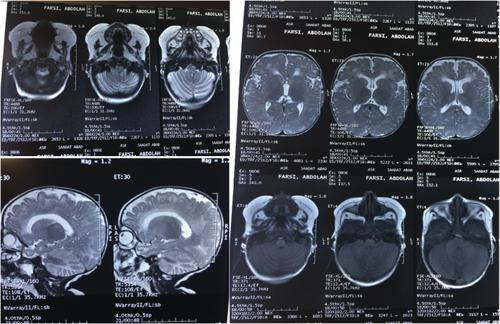

半乳糖血症是一种罕见的常染色体隐性代谢性疾病,主要有四种类型,其中经典半乳糖血症最为常见。这些患者有半乳糖-1-磷酸-尿苷基转移酶缺乏症。我们报告一例婴儿谁是入院喂养不良,嗜睡,和体重增加不佳。根据临床症状和实验室检查结果,该患者被认为患有代谢紊乱。患者有一些不寻常的表现,如需要输血的巨细胞性贫血,需要碳酸氢盐治疗的反复代谢性酸中毒,以及神经发育迟缓,导致作者做出不同的诊断并怀疑是线粒体疾病。最后,在输血前的一次评估中,检测到高半乳糖-1磷酸,并开始无半乳糖饮食,导致孩子的神经和身体。全外显子组测序(WES)也显示GALT (c.794)可能存在致病性纯合突变C>;G, p. Pro265Arg)确认经典半乳糖血症的诊断。在伊朗,全球新生儿代谢筛查未针对半乳糖血症进行,这导致受影响患者的诊断较晚。因此,我们建议在伊朗的新生儿代谢筛查中增加半乳糖血症。

Galactosemia is a rare autosomal recessive metabolic disorder with four main types, and classic galactosemia is the most prevalent. These patients have galactose-1-phosphate-uridyltransferase deficiency. We report on a case of an infant who was admitted with poor feeding, lethargy, and poor weight gain. Based on the clinical symptoms and laboratory findings, the patient was considered to have a metabolic disorder. The patient had unusual presentations such as macrocytic anemia requiring blood transfusions, repeatedly metabolic acidosis requiring bicarbonate therapy and failure to thrive in addition to neurodevelopmental delay which led the authors to different diagnoses and suspect to mitochondrial disorders. Finally, in one of the assessments before blood transfusion, a high galactose-1 phosphate was detected, and galactose-free diet was started which led to neurologic and physical of the child. The whole-exome sequencing (WES) also revealed a likely pathogenic homozygous mutation in GALT (c.794 C>G, p. Pro265Arg) confirming the diagnosis of classic galactosemia. In Iran, global neonatal metabolic screening is not done for galactosemia which results in late diagnosis of the affected patients. So, we suggest adding galactosemia to neonatal metabolic screening in Iran.